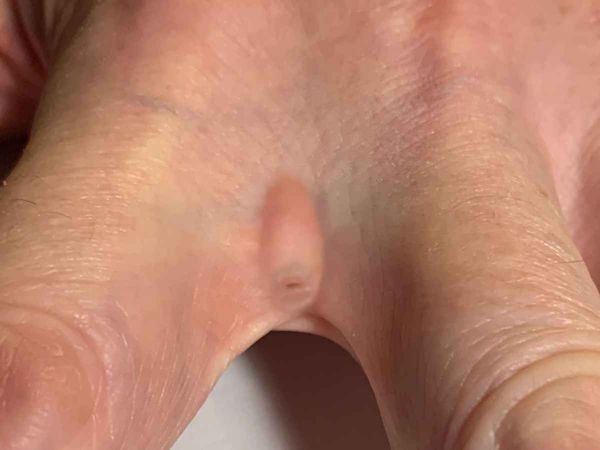

Een kuiltje (pit) in de huid, soms 2 openingen of deukjes, aan de onderkant en aan de bovenkant, verbonden door een mini-fisteltje, en meestal omgeven door zwelling en/of roodheid. Soms zitten de haren of haar er nog in. Het kan ontsteken en secundair geïnfecteerd raken, er kan een abces of grotere fistel ontstaan, die doorbreekt van palmair/plantair naar dorsaal, zelfs progressie naar een osteomyelitis is beschreven.

Interdigitale sinus pilonidalis